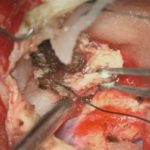

摘出 中

摘出 後